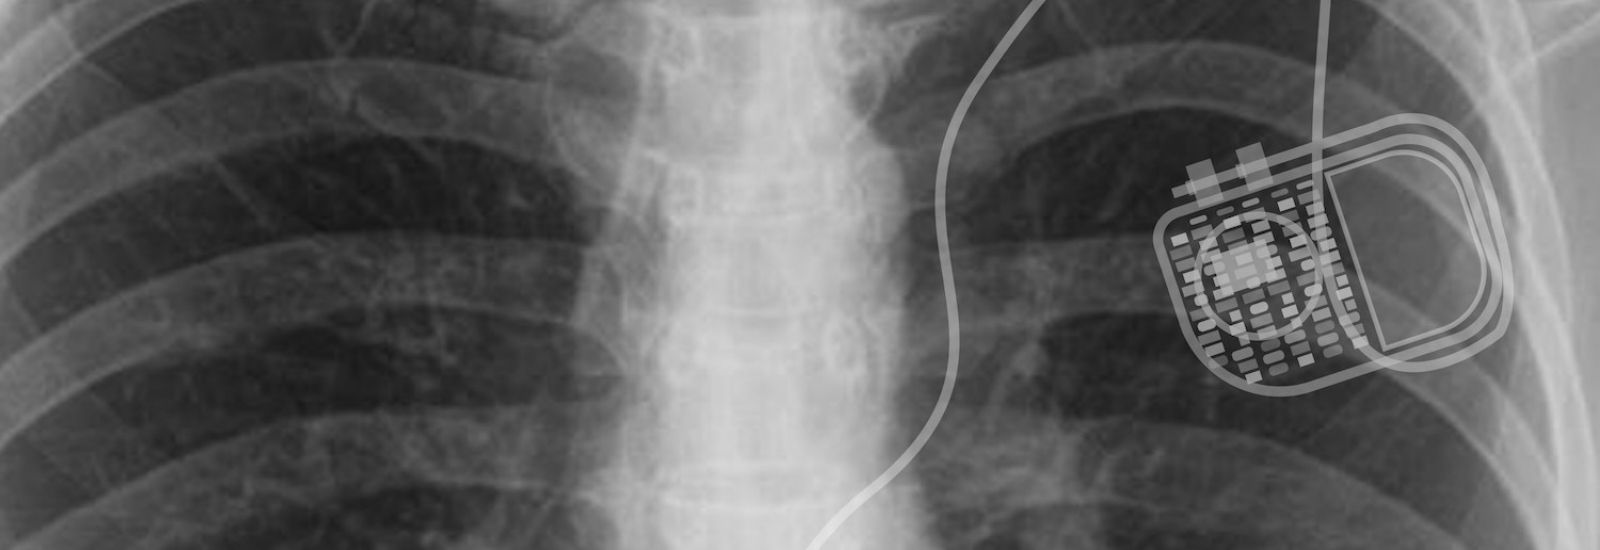

An Implantable Cardioverter Defibrillator (ICD) is a small, advanced device designed to detect and correct life-threatening heart rhythms such as ventricular tachycardia (VT) or ventricular fibrillation (VFib). These arrhythmias can lead to sudden cardiac arrest if not treated promptly.

How an ICD Works

The ICD procedure is performed in a cardiac catheterization or electrophysiology lab under local anesthesia with sedation:

1. A small incision is made near the collarbone

2. Leads are threaded through a vein into the heart to monitor electrical activity

3. The ICD device is connected to the leads and placed in a pocket under the skin

4. The device continuously monitors the heart rhythm and delivers a shock or pacing therapy when a dangerous arrhythmia is detected